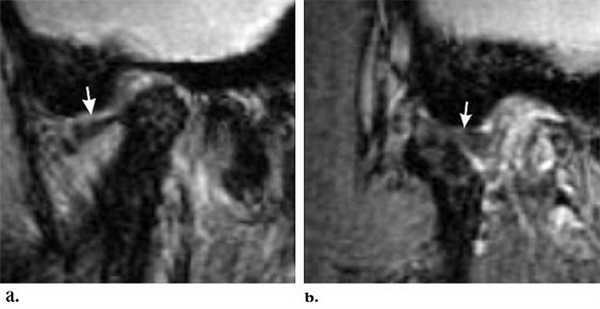

Во время проведения УЗИ на экране монитора во всех случаях хорошо визуализировались головка нижней челюсти, суставной диск, определялось его патологическое положение, измерялась степень смещения диска на всех этапах исследования. Следует отметить, что задние отделы суставного диска и головки нижней челюсти не всегда достаточно хорошо визуализировались, но, поскольку у всех наших пациентов наблюдалось переднее смещение суставного диска, контроль за нормализацией его положения был всегда возможен. После нескольких атропункций у 56 человек положение суставного диска нормализовалось, что подтверждается результатами УЗИ (рис. 2). Рисунок 2. Репозиция суставного диска ВНЧС у пациентов с невправляемым его смещением с помощью метода гидравлического прессинга под контролем УЗИ (пример 1). а — суставной диск смещен кпереди и деформирован. Рисунок 2. Репозиция суставного диска ВНЧС у пациентов с невправляемым его смещением с помощью метода гидравлического прессинга под контролем УЗИ (пример 1). б — после артропункции и гидравлической репозиции: суставной диск расправлен и равномерно распределен над головкой нижней челюсти. Рисунок 2. Репозиция суставного диска ВНЧС у пациентов с невправляемым его смещением с помощью метода гидравлического прессинга под контролем УЗИ (пример 2). а — суставной диск смещен кпереди и деформирован. Рисунок 2. Репозиция суставного диска ВНЧС у пациентов с невправляемым его смещением с помощью метода гидравлического прессинга под контролем УЗИ (пример 2). б — после артропункции и гидравлической репозиции: суставной диск расправлен и равномерно распределен над головкой нижней челюсти.